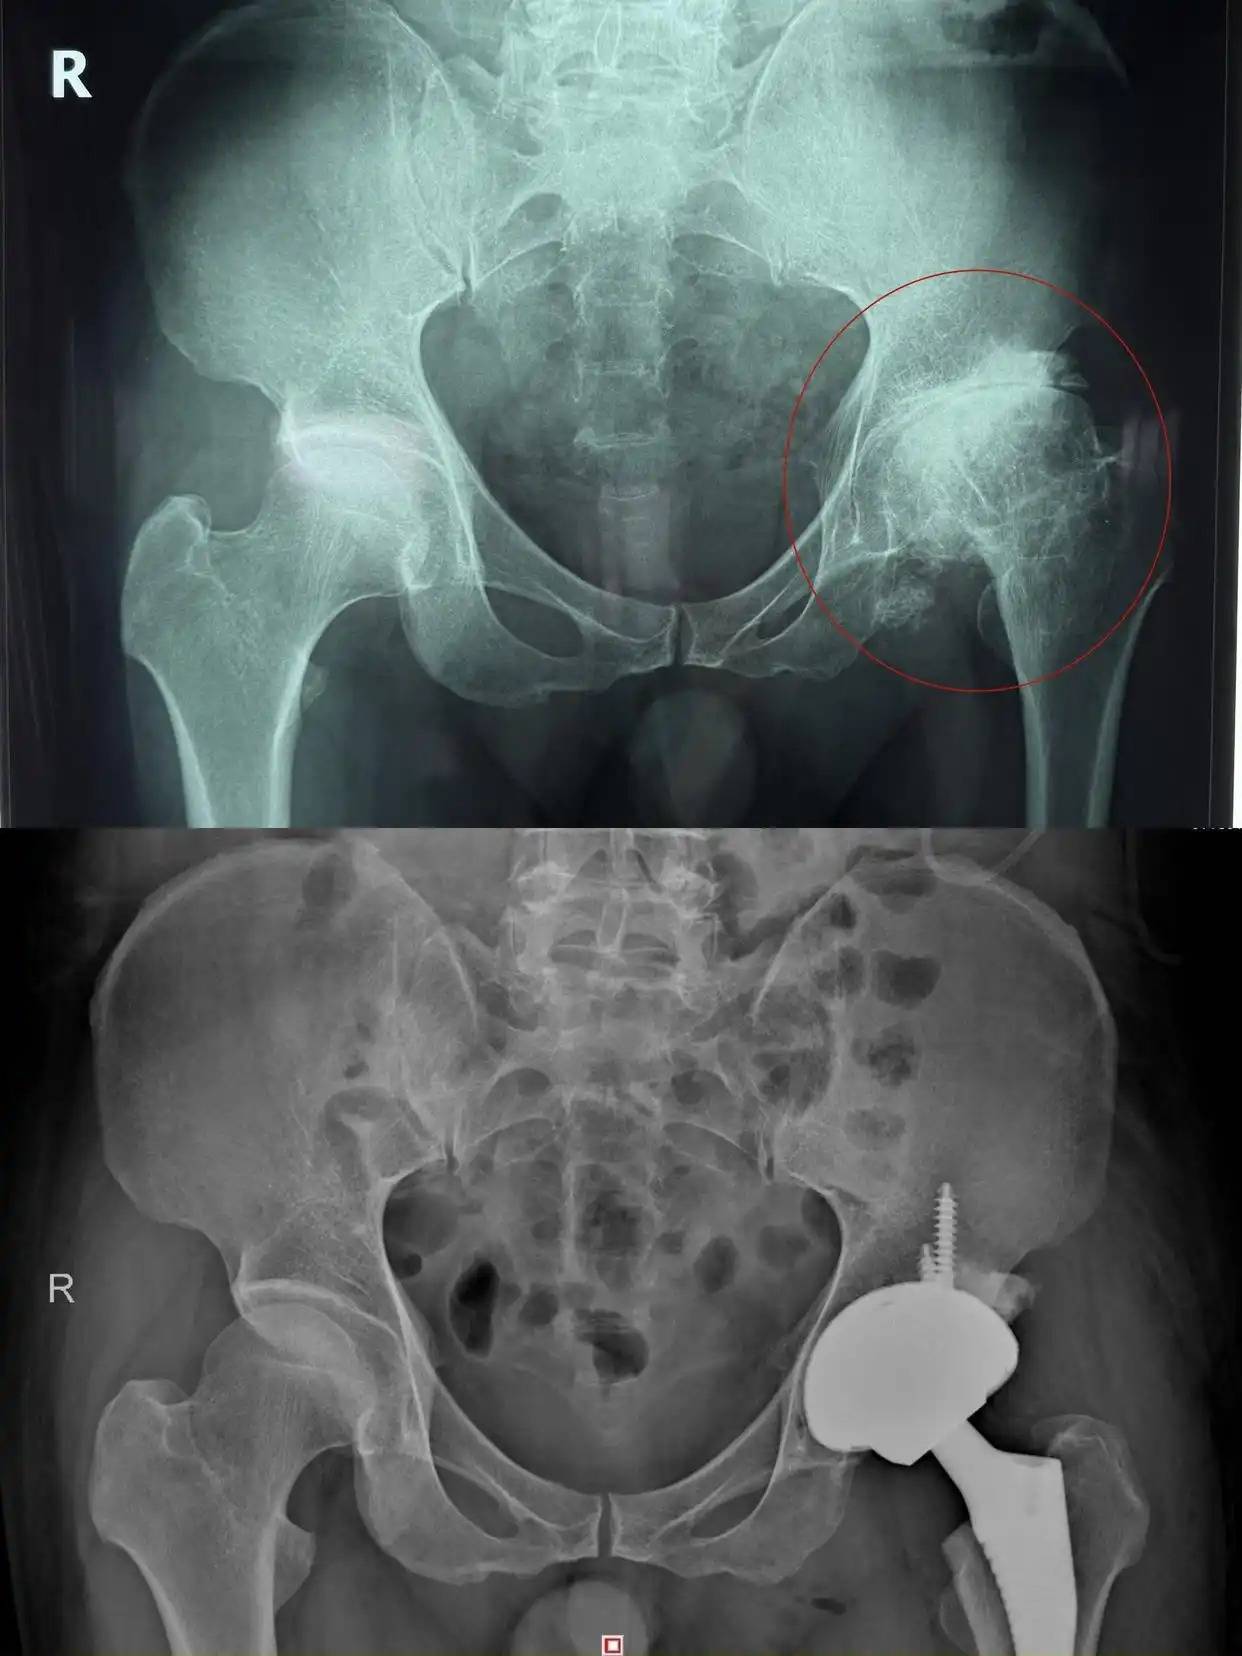

家住益阳的52岁杨先生左髋部反复疼痛20余年,近期疼痛加剧、关节活动严重受限,就医确诊为股骨头坏死晚期,近日在湖南省第二人民医院骨关节运动医学科,接受全髋关节置换手术才得以缓解,目前正在进一步康复中。医生提醒十大配资平台,长期激素使用是股骨头坏死的高危因素,早识别、早干预至关重要。

第三,晚期(塌陷严重、疼痛剧烈):全髋关节置换术是目前最成熟、效果最确切的治疗方式,术后可快速恢复行走与日常活动,生活质量显著提高。